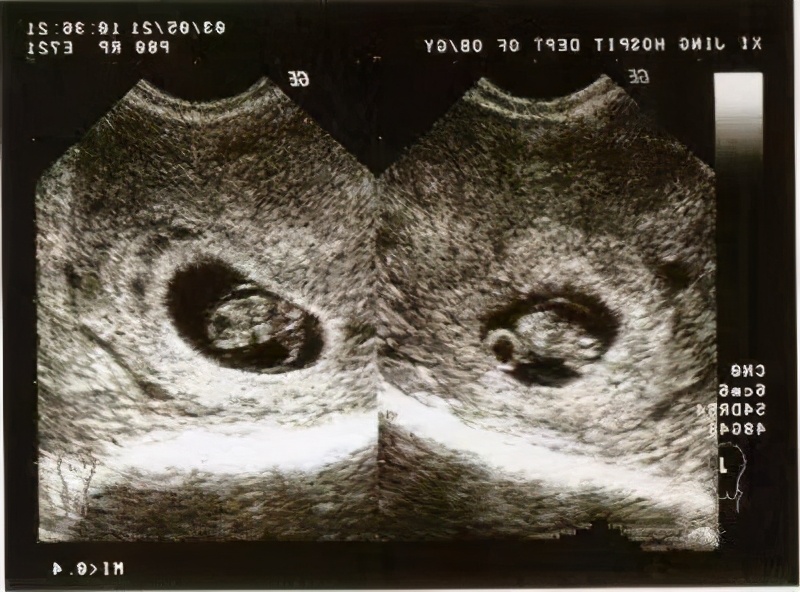

早期到医院做什么检查?早期到医院需要建立相关的孕期保健资料或者健康档案,这样就不会错过重要的检查。医生会抽血完善相关的检查,有一项重要的检查是传染性疾病的检查。对于本来就有传染病或者孕妇不清楚是否患病的,早期发现早期治疗是可以阻断传播的,从而避免将一些传染病传给胎儿。还有,通过孕早期的检查,医生会初步判断孕妇是否适宜继续妊娠或者需要终止妊娠,特别是高龄孕妈妈和有某些合并症的孕妈妈。早期的B超可以排除异位妊娠,也是一项很重要的检查。